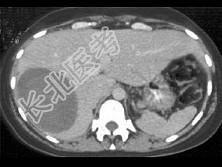

- 单项选择题患者40岁,女性, 肝区偶然发现一个团块,结合图像, 最可能的诊断是 ( )

A、阿米巴肝脓肿

B、肝包虫囊肿

C、肝癌

D、皮样囊肿

E、肝囊肿